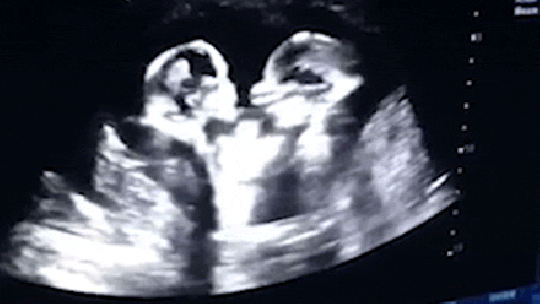

Elképesztő felvételeket sikerült rögzíteni egy ultrahangos vizsgálat során, amikor két baba az anyaméhben szabályosan pofozni kezdte egymást – írja a Metro nevű brit bulvárlap.

A 28 éves kínai férfi, akire Mr Taóként hivatkoznak Jincsuan városában vitte vizsgálatra a feleségét, aki ikreket hord a szíve alatt. Az ultrahangon az látható, ahogy a két kislány szabályosan harcol egymással. Úgy néz ki, hogy a babák már a születésük előtt híressé válnak, ám azt még nem lehet tudni, milyen lesz a kapcsolatuk egymással, miután világra jöttek.